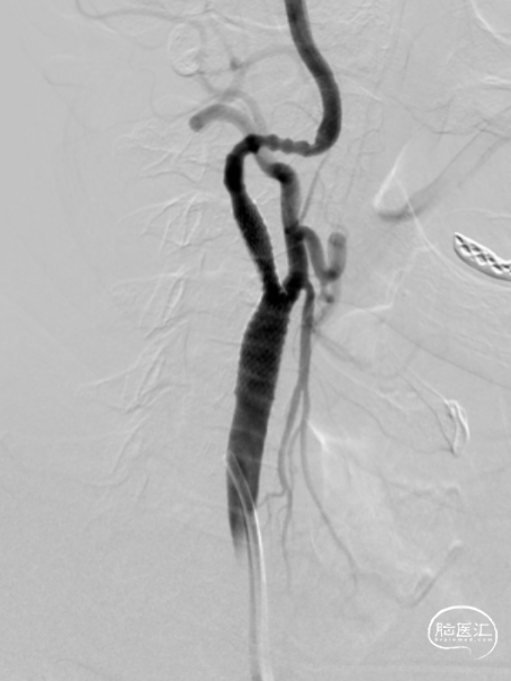

术前评估:术前MRA及造影检查显示右侧颈内动脉走行迂曲,起始段重度狭窄(狭窄率大于90%),测量得患者颈总动脉直径8.0mm,颈内动脉直径4.0mm左右。右侧大脑前未显影,左侧颈动脉造影示前交通动脉开放,向对侧大脑前动脉代偿供血,后交通开放,向右侧大脑中动脉少量代偿供血。

结论:双侧颈动脉硬化并斑块形成,右颈内动脉起始段狭窄(狭窄率70-99%)。

术中置入0.014mm微导丝通过狭窄处至远端,沿导丝置入直径5mm保护伞至右侧颈内动脉C1段远端,因动脉迂曲,保护伞通过困难,并有一定程度血管痉挛。

2

沿导丝置入4*30mm AVIATOR PLUS球囊预扩张狭窄病变,狭窄改善欠佳,再用6*30mm AVIATOR PLUS球囊扩张病变后置入9*40mm PRECISE支架并释放。